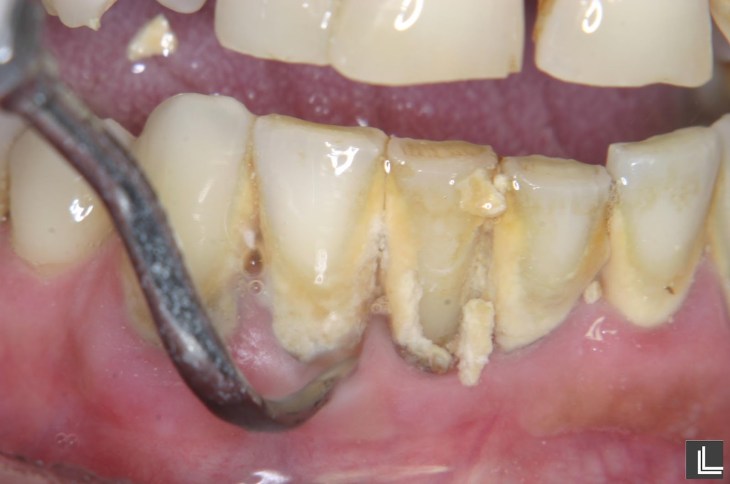

| Fig.1. Antes e depois num paciente com Periodontite activa |